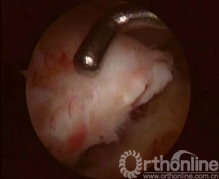

患者取仰卧患膝屈曲90°位,连续硬膜外麻醉,患肢大腿根部上气囊止血带,70Kpa,重力关节灌洗液悬挂在高于术膝1.2m处,常规前内、前外侧入路置入关节镜及工具。行关节镜常规入路清除关节内积血及凝血块,确诊交叉韧带撕脱骨折,处理半月板等其他损伤,仔细清理骨床及撕脱骨块。胫骨髁间隆突前区的骨折,应仔细清除血凝块及游离碎骨块,用关节镜刮勺略加深胫骨侧骨创面(图1)。陈旧性骨折不愈合的病例需使骨折面的两面新鲜化。撕脱骨片已前翘畸形愈合的病例需使愈合的后端再骨折并使创面新鲜化。

图1 图2